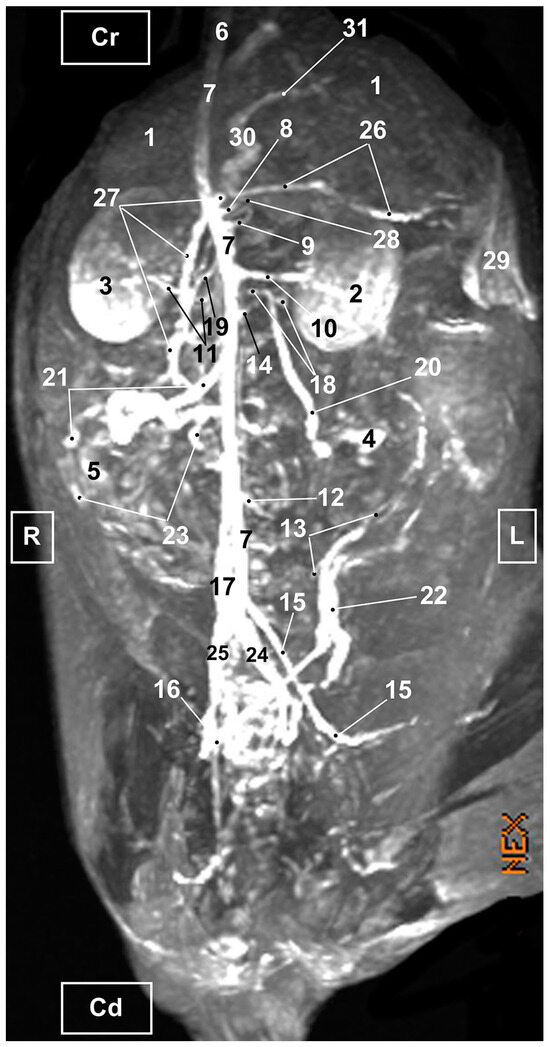

3.1. Gross Dissections

3.1.1. Arterial System

3.1.2. Venous System